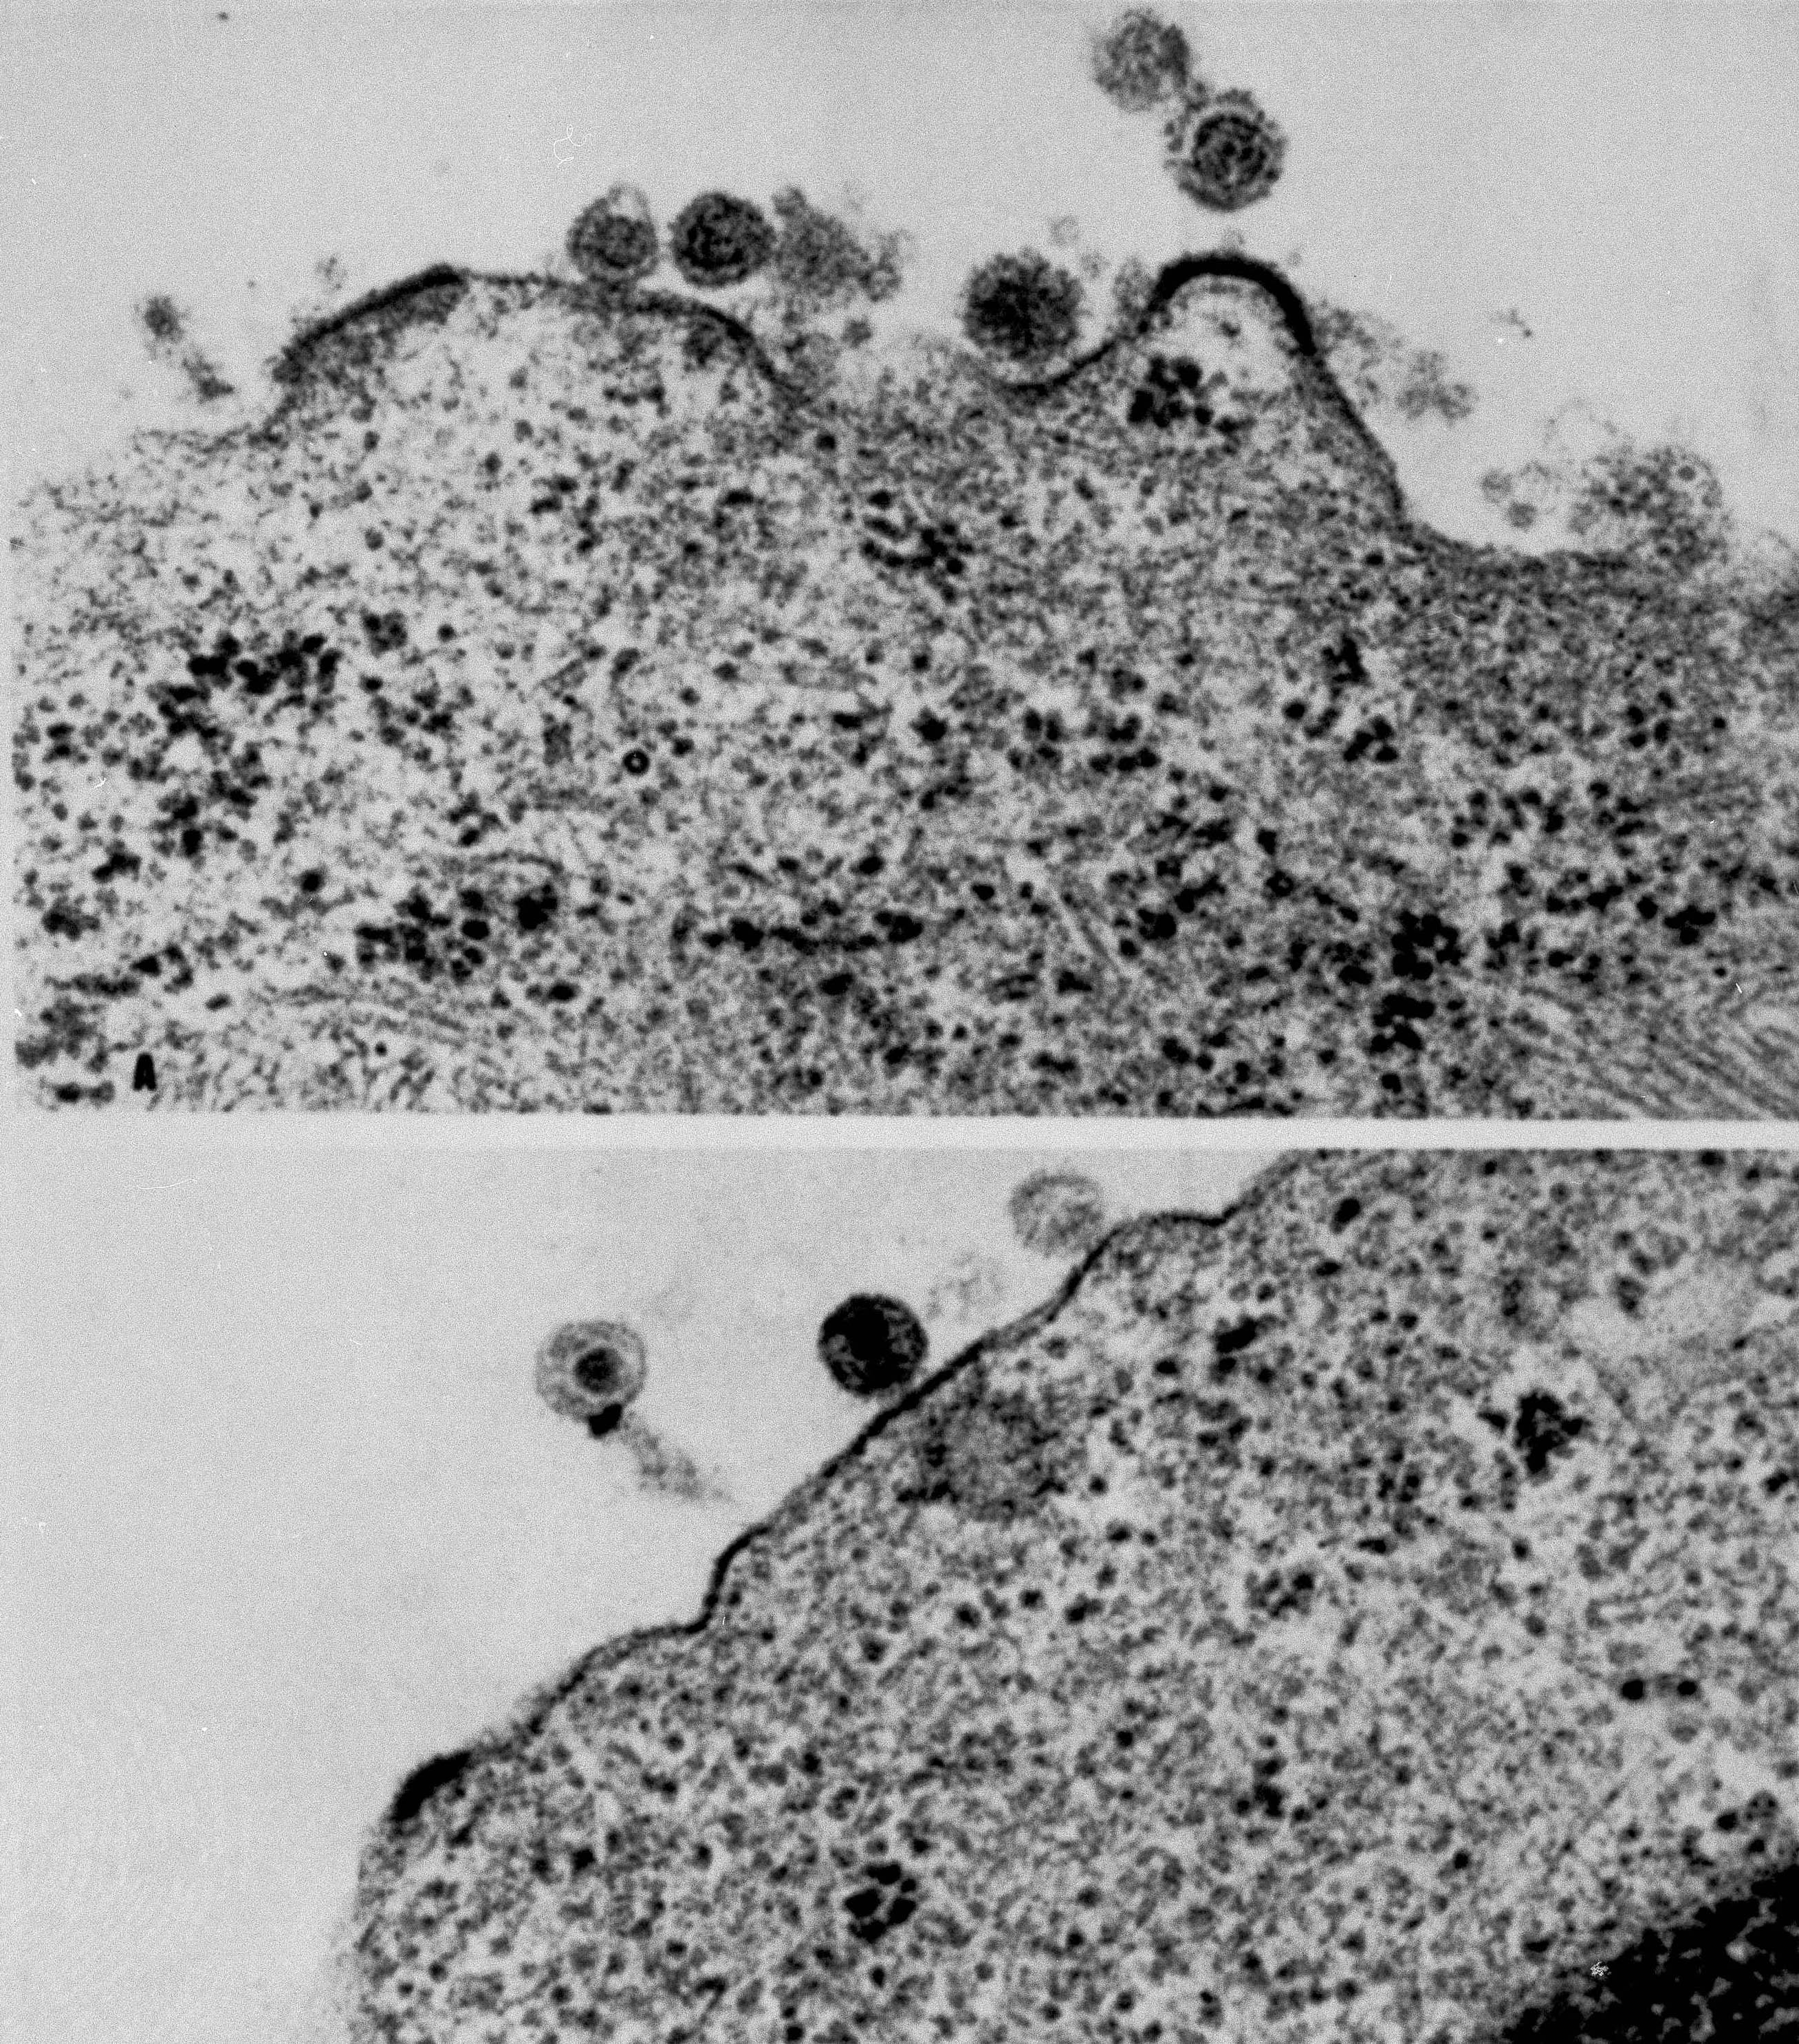

Although it is unclear if HTLV-3 and LAV are the same viruses, it appears that scientists have identified, isolated, grown and taken electron microscope pictures of a virus or viruses that may cause AIDS.